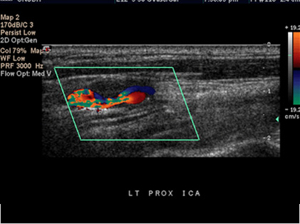

- 도플러 초음파 검사 (Duplex ultrasound)

- 하지정맥류 진단에 가장 중요하고 기본이 되는 비침습 검사입니다.

- 혈관 초음파로 혈관 구조를 확인하고 도플러를 통해 혈액의 흐름 방향, 속도, 역류 여부 및 역류 시간을 측정합니다.

- 이 검사를 통해 정맥 내 판막 손상 부위에서 혈액이 역류하는 정도를 평가하고, 정맥류의 원인이 되는 혈관을 정확히 찾아낼 수 있습니다.

- 도플러 초음파 검사 (혈관초음파)

- 가장 기본이며 핵심적인 검사입니다.

- 혈관 내 혈류의 방향, 속도, 역류 여부와 역류 시간을 직접 측정할 수 있습니다.

- 정맥 판막의 손상 부위를 확인하고, 혈액이 역류하는 정도를 정량적으로 평가합니다.

- 정맥류의 원인이 되는 혈관을 정확히 찾아내고, 혈관 구조와 기능을 동시에 볼 수 있어 진단과 치료 계획 수립에 가장 효과적입니다.

- 도플러 초음파 검사 (Doppler Ultrasound)

- 일반 초음파의 원리에 도플러 효과를 적용한 검사로, 움직이는 혈액의 속도와 방향을 실시간으로 측정할 수 있습니다.

- 혈관 내 혈류의 특성을 분석해 혈류가 정상적으로 흐르는지, 역류나 협착이 있는지 평가할 수 있습니다.

- 혈관의 기능적 상태를 파악하는 데 중요한 역할을 하며, 하지정맥류, 동맥 협착, 혈전 등 혈관 질환 진단에 쓰입니다.